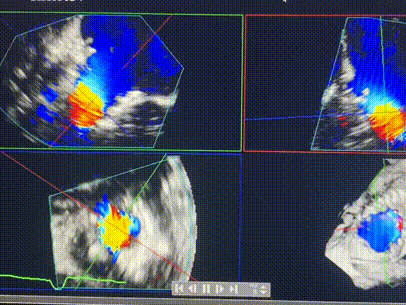

術前超聲提示重度三尖瓣反流

接受本次LuX-Valve Plus治療的是一位三尖瓣重度反流的高齡女性,患者早前曾由于二尖瓣疾病行經(jīng)導管二尖瓣置換術,植入Tendyne瓣膜一枚,且有ICD植入史。術前CT分析結果顯示,瓣環(huán)大小為47.6mm,血管無明顯迂曲和鈣化。由于患者三尖瓣解剖結構復雜,二尖瓣位人工瓣膜造成的超聲偽影和ICD導線的干擾使得歐洲沒有其他合適的商業(yè)化和臨床試驗的產(chǎn)品可以對其進行治療。經(jīng)過Rodrigo Estévez-Loureiro教授團隊的詳盡術前評估,認為LuX-Valve Plus經(jīng)導管三尖瓣置換系統(tǒng)可以對該患者進行有效的治療。因此,Rodrigo Estévez-Loureiro教授團隊最終決定使用這一中國創(chuàng)新器械為患者進行手術。法國波爾多里爾大學附屬醫(yī)院的Thomas Modine教授與加拿大圣保羅醫(yī)院的Anson Cheung教授全程線下指導本次手術。